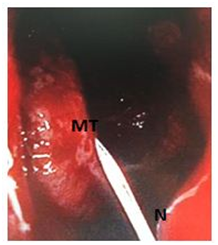

Figure 3A Conchopexy suture - Needle through the head of the middle turbinate.

(MT: Middle Turbinate; MM: Middle Meatus; NS: Nasal Septum; N: Needle)

The needle is introduced into the left nasal cavity oriented vertically, visualized with a 0˚ nasal telescope, and passed through the head of the middle turbinate, septum and the contralateral middle turbinate in a single pass. It is then brought back to the right middle turbinate and passed through the septum to the initial side to be knotted with direct visualization. This technique has been criticized for its likely effect on olfaction but there are studies which confirm that it does not impair the function of olfaction.3 Endoscopic Conchopexy Suture has also been considered a difficult technical and lengthens the operating time due to the need to tie inside the nasal cavity, but a new technique has simplified this process of suture to avoid knot-tying within the nasal cavity using a monofilament barbed suture with knot tied.1 This technique is mainly indicated to cases of Endoscopic Surgery with an unstable middle turbinate and also if a septoplasty ES performed. In these cases the Bolgerization technique can produce major injure of the middle turbinate and a septal perforation, hence it is preferred to perform a conchopexy suture avoiding these complications. Moreover, Conchopexy Suture is more comfortable for patients because it needs no postoperative removable nasal packing.